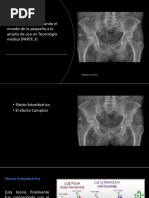

Efecto Compton

Arthur Holly Compton Sus estudios de los rayos X le llevaron a descubrir el 1923 el

denominado efecto Compton. Efecto Compton: es

el cambio de longitud de onda de la radiación

electromagnética de alta energía al ser dispersada

por los electrones El descubrimiento de este

efecto confirmó que la radiación electromagnética

tiene propiedades tanto de onda como de

partículas, un principio central de la teoría

cuántica

El efecto Compton se presenta entre los rayos X de moderada energía y los electrones de

las capas más externas. Causa la ionización del átomo diana, cambio en la dirección del

rayo X y la reducción de la energía del mismo. La longitud de onda del rayo X dispersado

es superior a la del rayo X incidente. La probabilidad de que un rayo X interaccione por

efecto Compton es aproximadamente la misma para los átomos diana de tejidos blandos y

hueso.

Esta probabilidad disminuye al aumentar la energía del rayo X. Los rayos X dispersos de

las interacciones Compton pueden producir un grave riesgo de

exposición a la radiación en la radiografía y, de forma particular, en la fluoroscopia. Una

gran cantidad de radiación puede ser dispersada desde el paciente durante la fluoroscopia.

Esta radiación es la fuente de la mayoría de exposición ocupacional a la radiación que

reciben los técnicos en radiología.

Efecto fotoeléctrico

Los rayos X en el rango diagnóstico también se someten a interacciones ionizantes con los

electrones de las capas más internas. El rayo X no se

dispersa, sino que se absorbe totalmente. El electrón

que abandona el átomo, denominado fotoelectrón;

escapa con una energía cinética igual a la diferencia

entre la energía del rayo X incidente y la energía de

unión del electrón. Una interacción fotoeléctrica no

puede manifestarse a menos que el rayo incidente

presente una energía igual o superior a la energía de

unión del electrón.